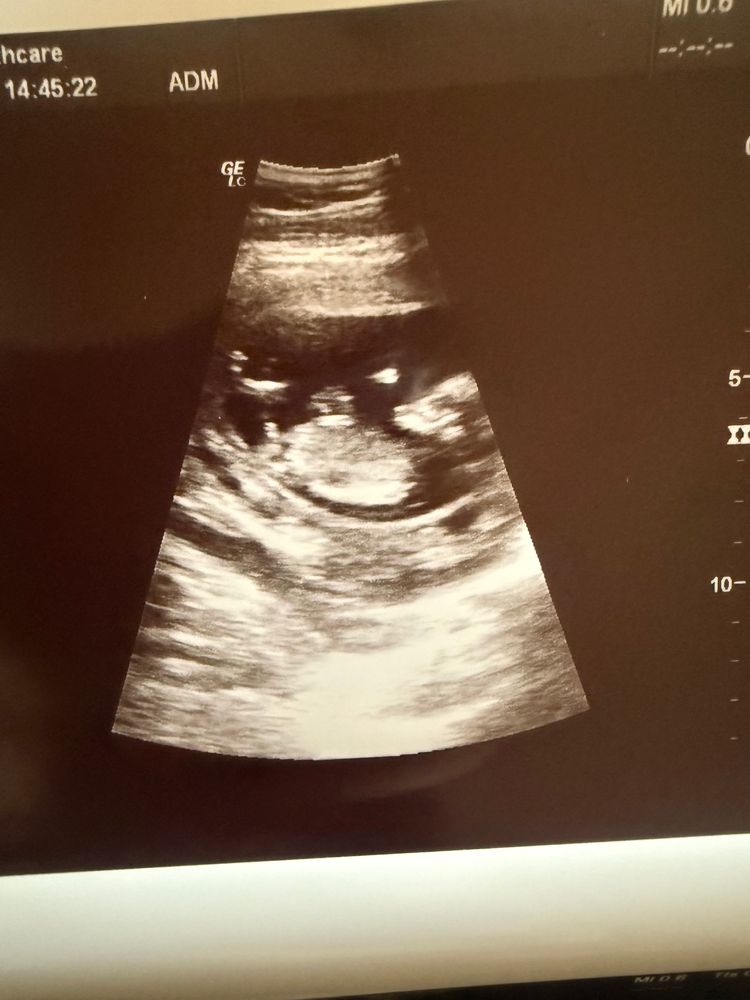

Мальчик или девочка

Мальчик я думаю 💙

Если это не пуповина то точно мальчик))

На мальчика похож

Вот с таким же половым бугорком у меня родилась девочка.))) так, что 50/50

Я бы сказала, что мальчик